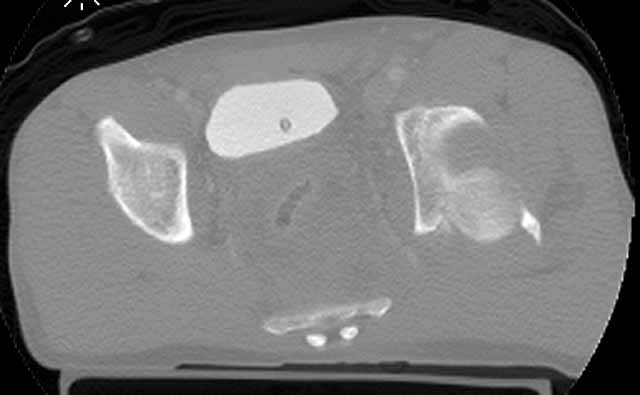

We initially did an ORIF of the femoral neck and then the head using a modified Smith-Petersen exposure with the patient positioned supine. The femoral head fracture fragment was without soft tissue attachments and removed temporarily. The ligamentum teres had been disrupted from its femoral head attachment so it was debrided. The dislocated head-neck fragment was then rotated out of the posterior impaction area, manipulated into the acetabulum preserving it s limited capsular remnants, rotated it to fit the neck, and then stabilized with screws inserted through stab wounds and guided by fluoroscopy. Then we reduced and used small screws to hold the previously removed femoral head fracture fragment.

For a variety of reasons we stopped at that, placed him in traction, and repeated his films and CT.

Two days later we returned to the OR and tried a closed manipulative reduction of the SI joint-iliac fracture but it failed, so we used the lateral (iliac) window of an ilioinguinal exposure to clean, reduce, and clamp the SI joint. We stabilized it with an iliosacral screw and closed.

Under the same anesthesia, we used a prone K-L exposure to reduce the impaction fragment, fold down the posterior wall, and hold it with a plate.

Here are the films....the staple lines mark his incisions.

CT Acet

We'll use ectopic bone prophylaxis and protect his weight bearing.